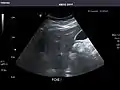

Kidneys: Right and left kidneys measure 11.5 cm and 12 cm in length respectively. No hydronephrosis. Small left lower pole kidney cyst.

Left kidney